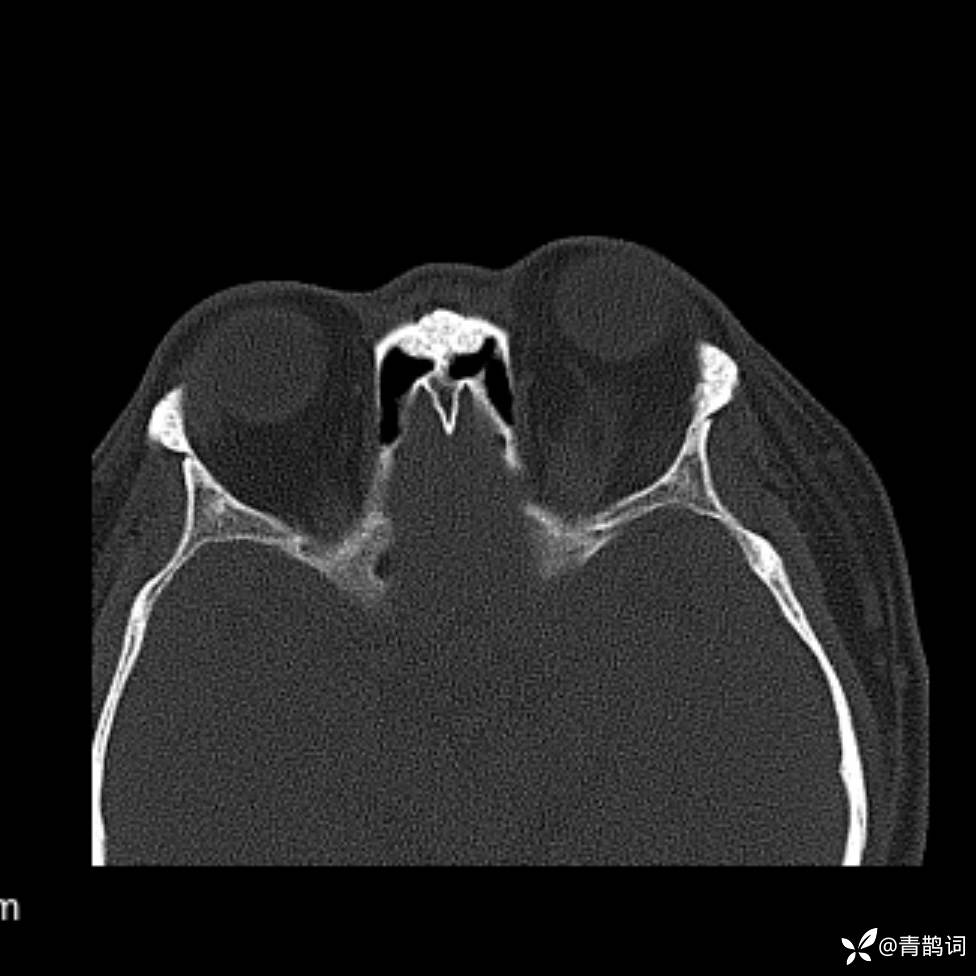

患者年龄:30岁。

患者性别:男。

简要病史:左颜面部肿胀2年,反复咳嗽咳痰,逐渐加重。

辅助检查

结合病史及影像学表现,期待评论区各位老师各抒己见~